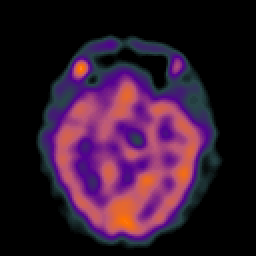

Hypertensive Encephalopathy, overlay -- Slice #10